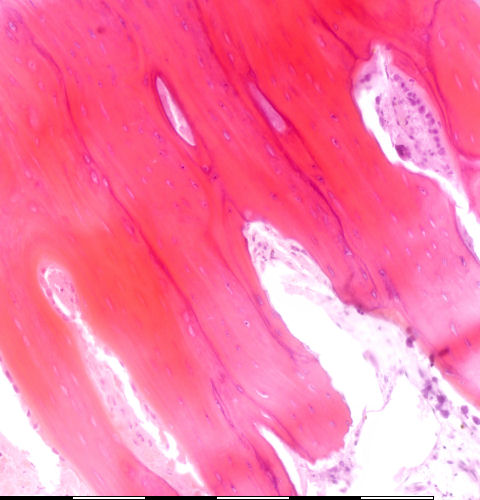

Medium magnification of immature bone

Beenhermoduleringseenhede / Bone-remodeling units Vulkonus: osteoblaste / Filling cone: osteoblasts Snykonus: osteoklaste / Cutting cone: osteoclasts Groeilyne / Growth reversal lines Endosteale selle / Endosteal cells Twee osteosiete in \'n lakunae / Two osteocytes in a lacunae Osteoied / Osteoid